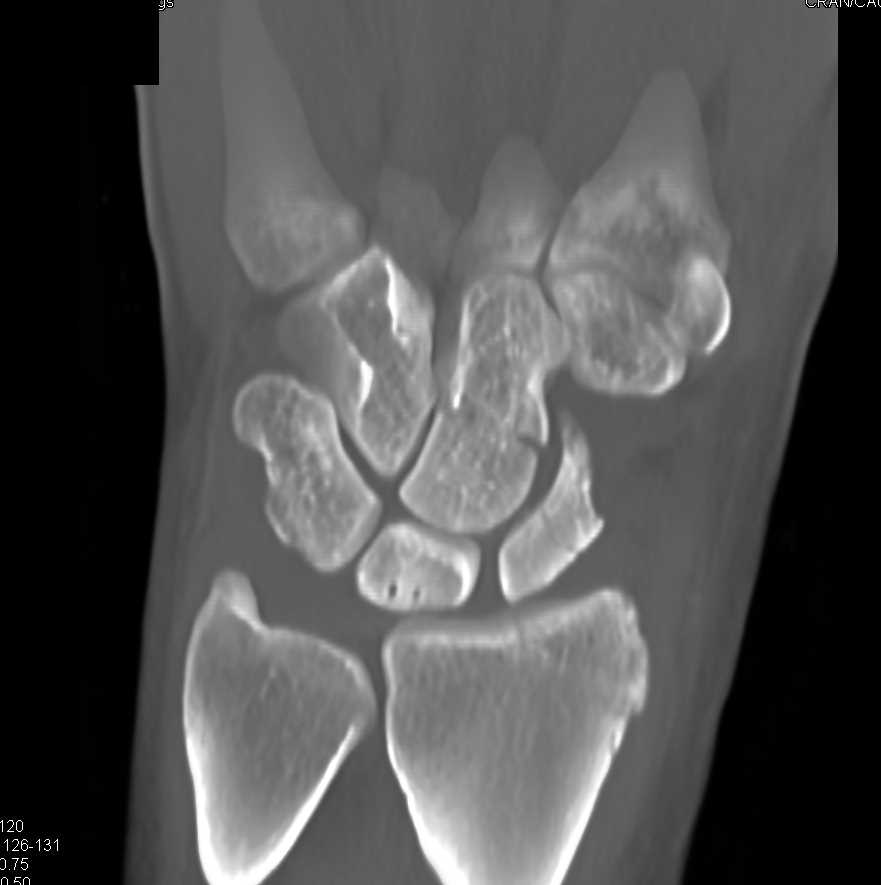

Multiple Carpal Fractures Including Scaphoid